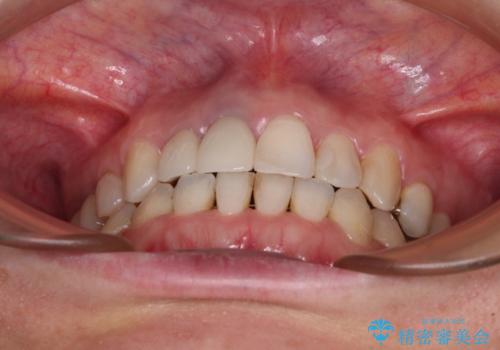

仕事がお忙しく、インビザラインをあまりしっかりと使用できなかったようで、何とか長い期間をかけて歯列を整えることができました。

磨きにくく、何度もむし歯治療を繰り返していた前歯をスッキリと整えることができました。